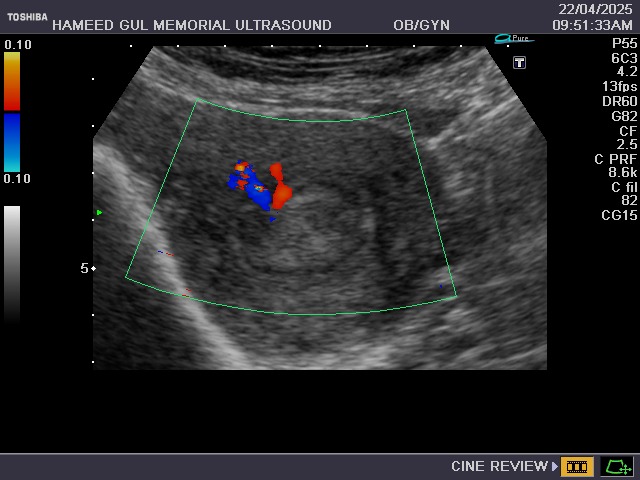

The female pelvic ultrasound that includes examination of the

uterus, ovaries, adnexa,

and cul-de-sac.